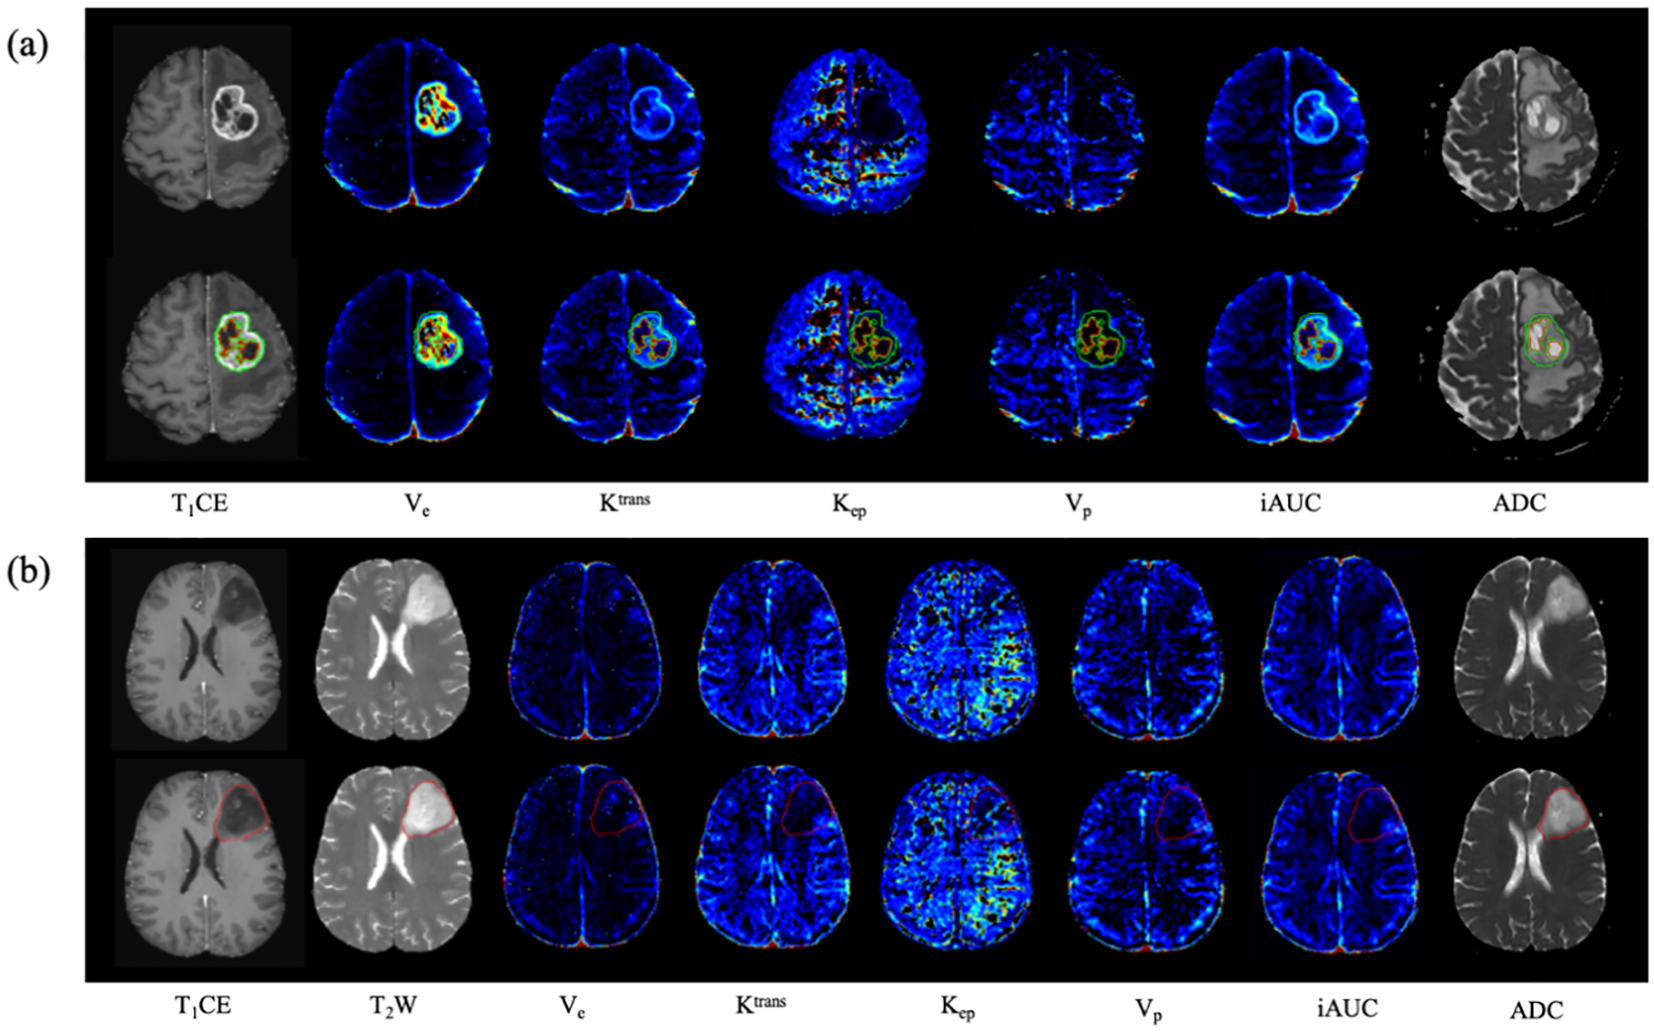

Figure 2

Examples of the automated segmentation and co‐registration with other sequences. (a) a case of glioblastoma. The lesion showed obvious enhancement, and tumor core was automatically segmented based on T1CE. (b) a case of diffuse astrocytoma (WHO 2 grade, IDH1-mut). The lesion showed no obvious enhancement, and tumor core was automatically segmented based on T2WI.